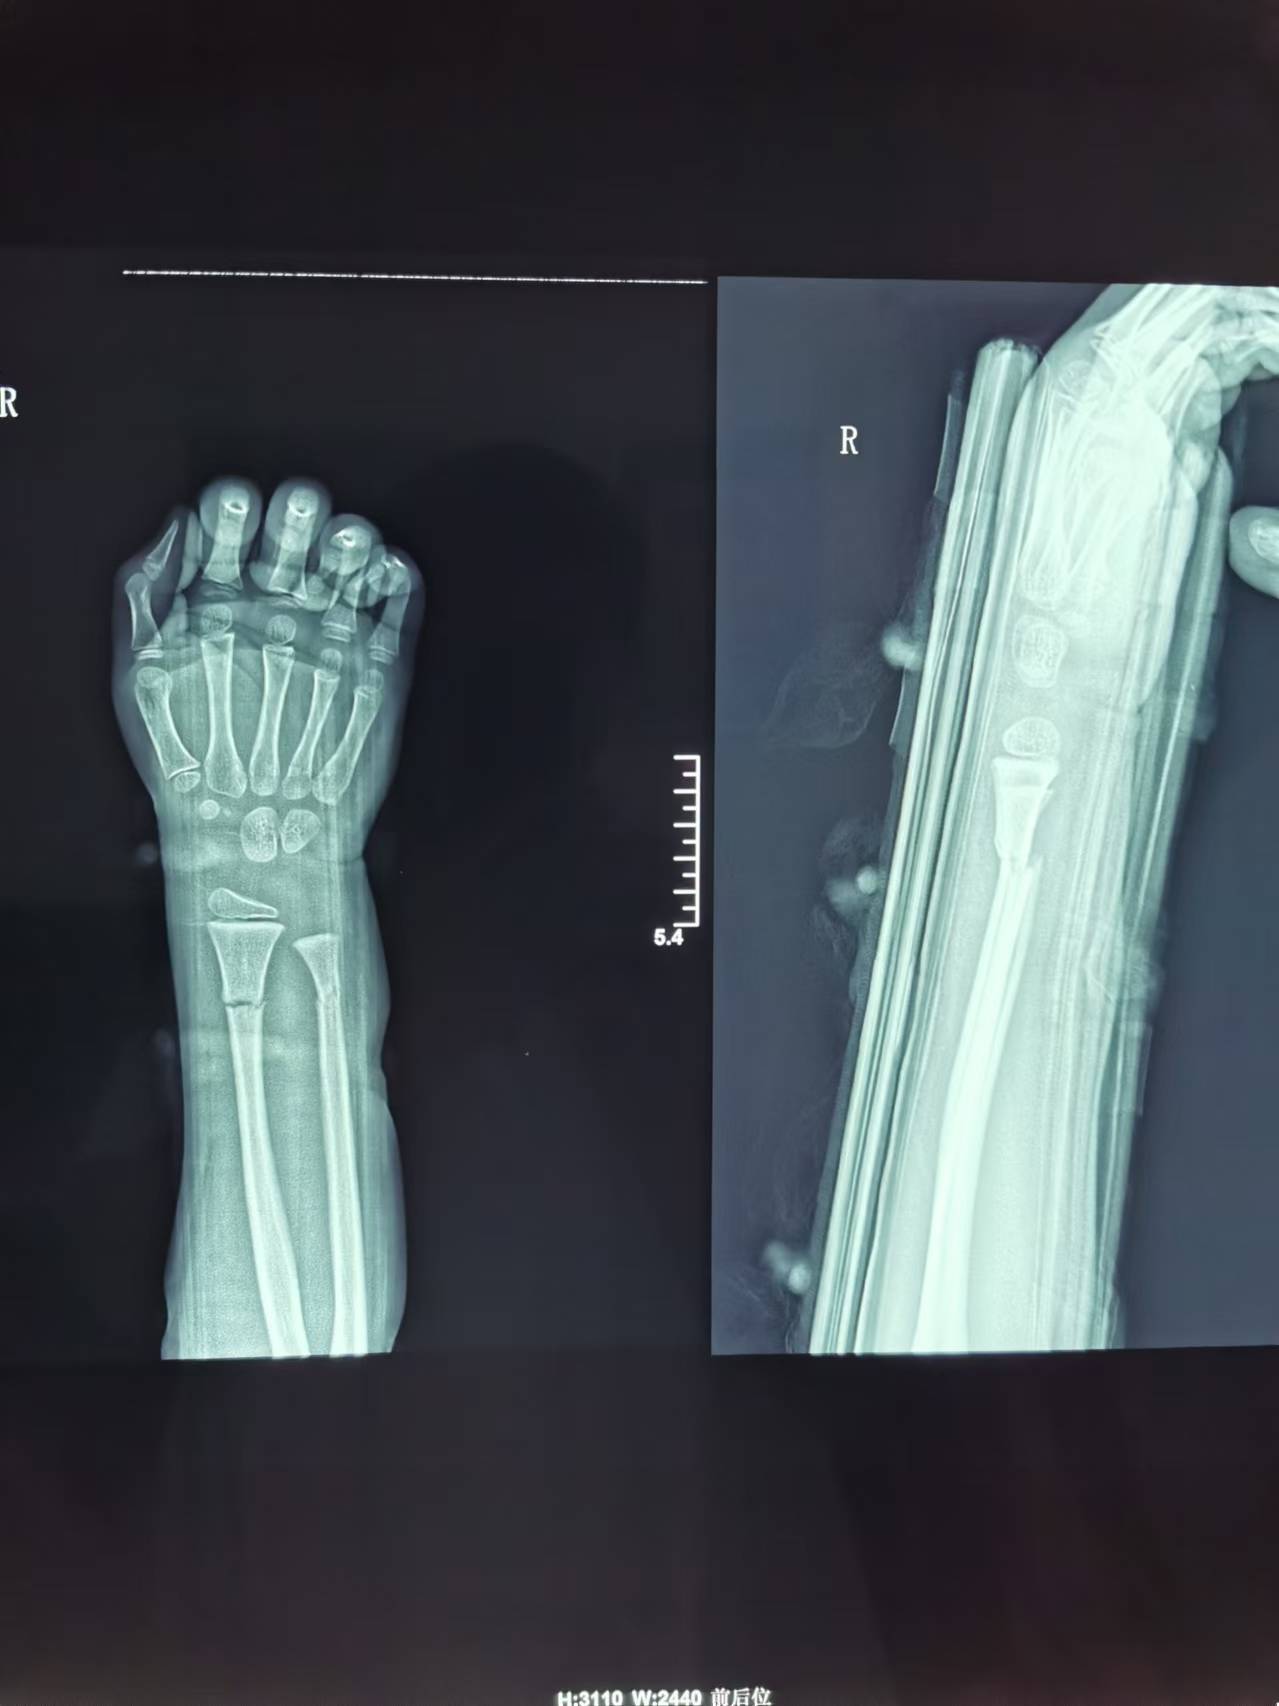

首页 > 张恒云工作室 > 影像资料 一